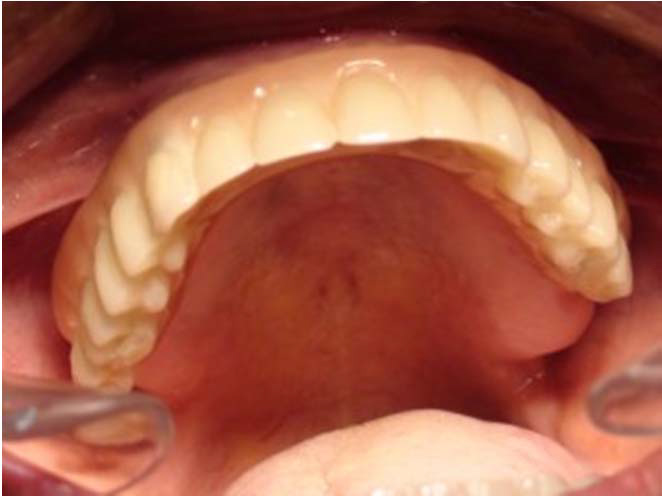

Bezzubá čelist je hlavní indikací pro ošetření pomocí implantátů. Zejména celkové zubní náhrady v dolní čelisti mají velice nízkou stabilitu a držení díky velkému úbytku kosti.

S pomocí zubních implantátů můžeme díky různým kotevním systémům (třmeny, kulové hlavy, Locatory) zajistit stabilitu a držení protézy nebo při použití většího počtu implantátů zhotovit pevné náhrady – můstky nalepené nebo našroubované na pevno na implantáty.

S těmito typy náhrad můžeme dosáhnout perfektní funkci, výbornou estetiku, fonetiku a současně zajistit u pacienta možnost dobré hygienickou péče a čištění, která je pro životnost implantátů velice důležitá.